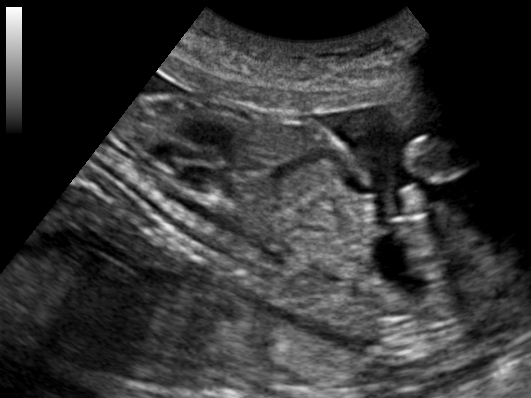

4. 추가 이미지